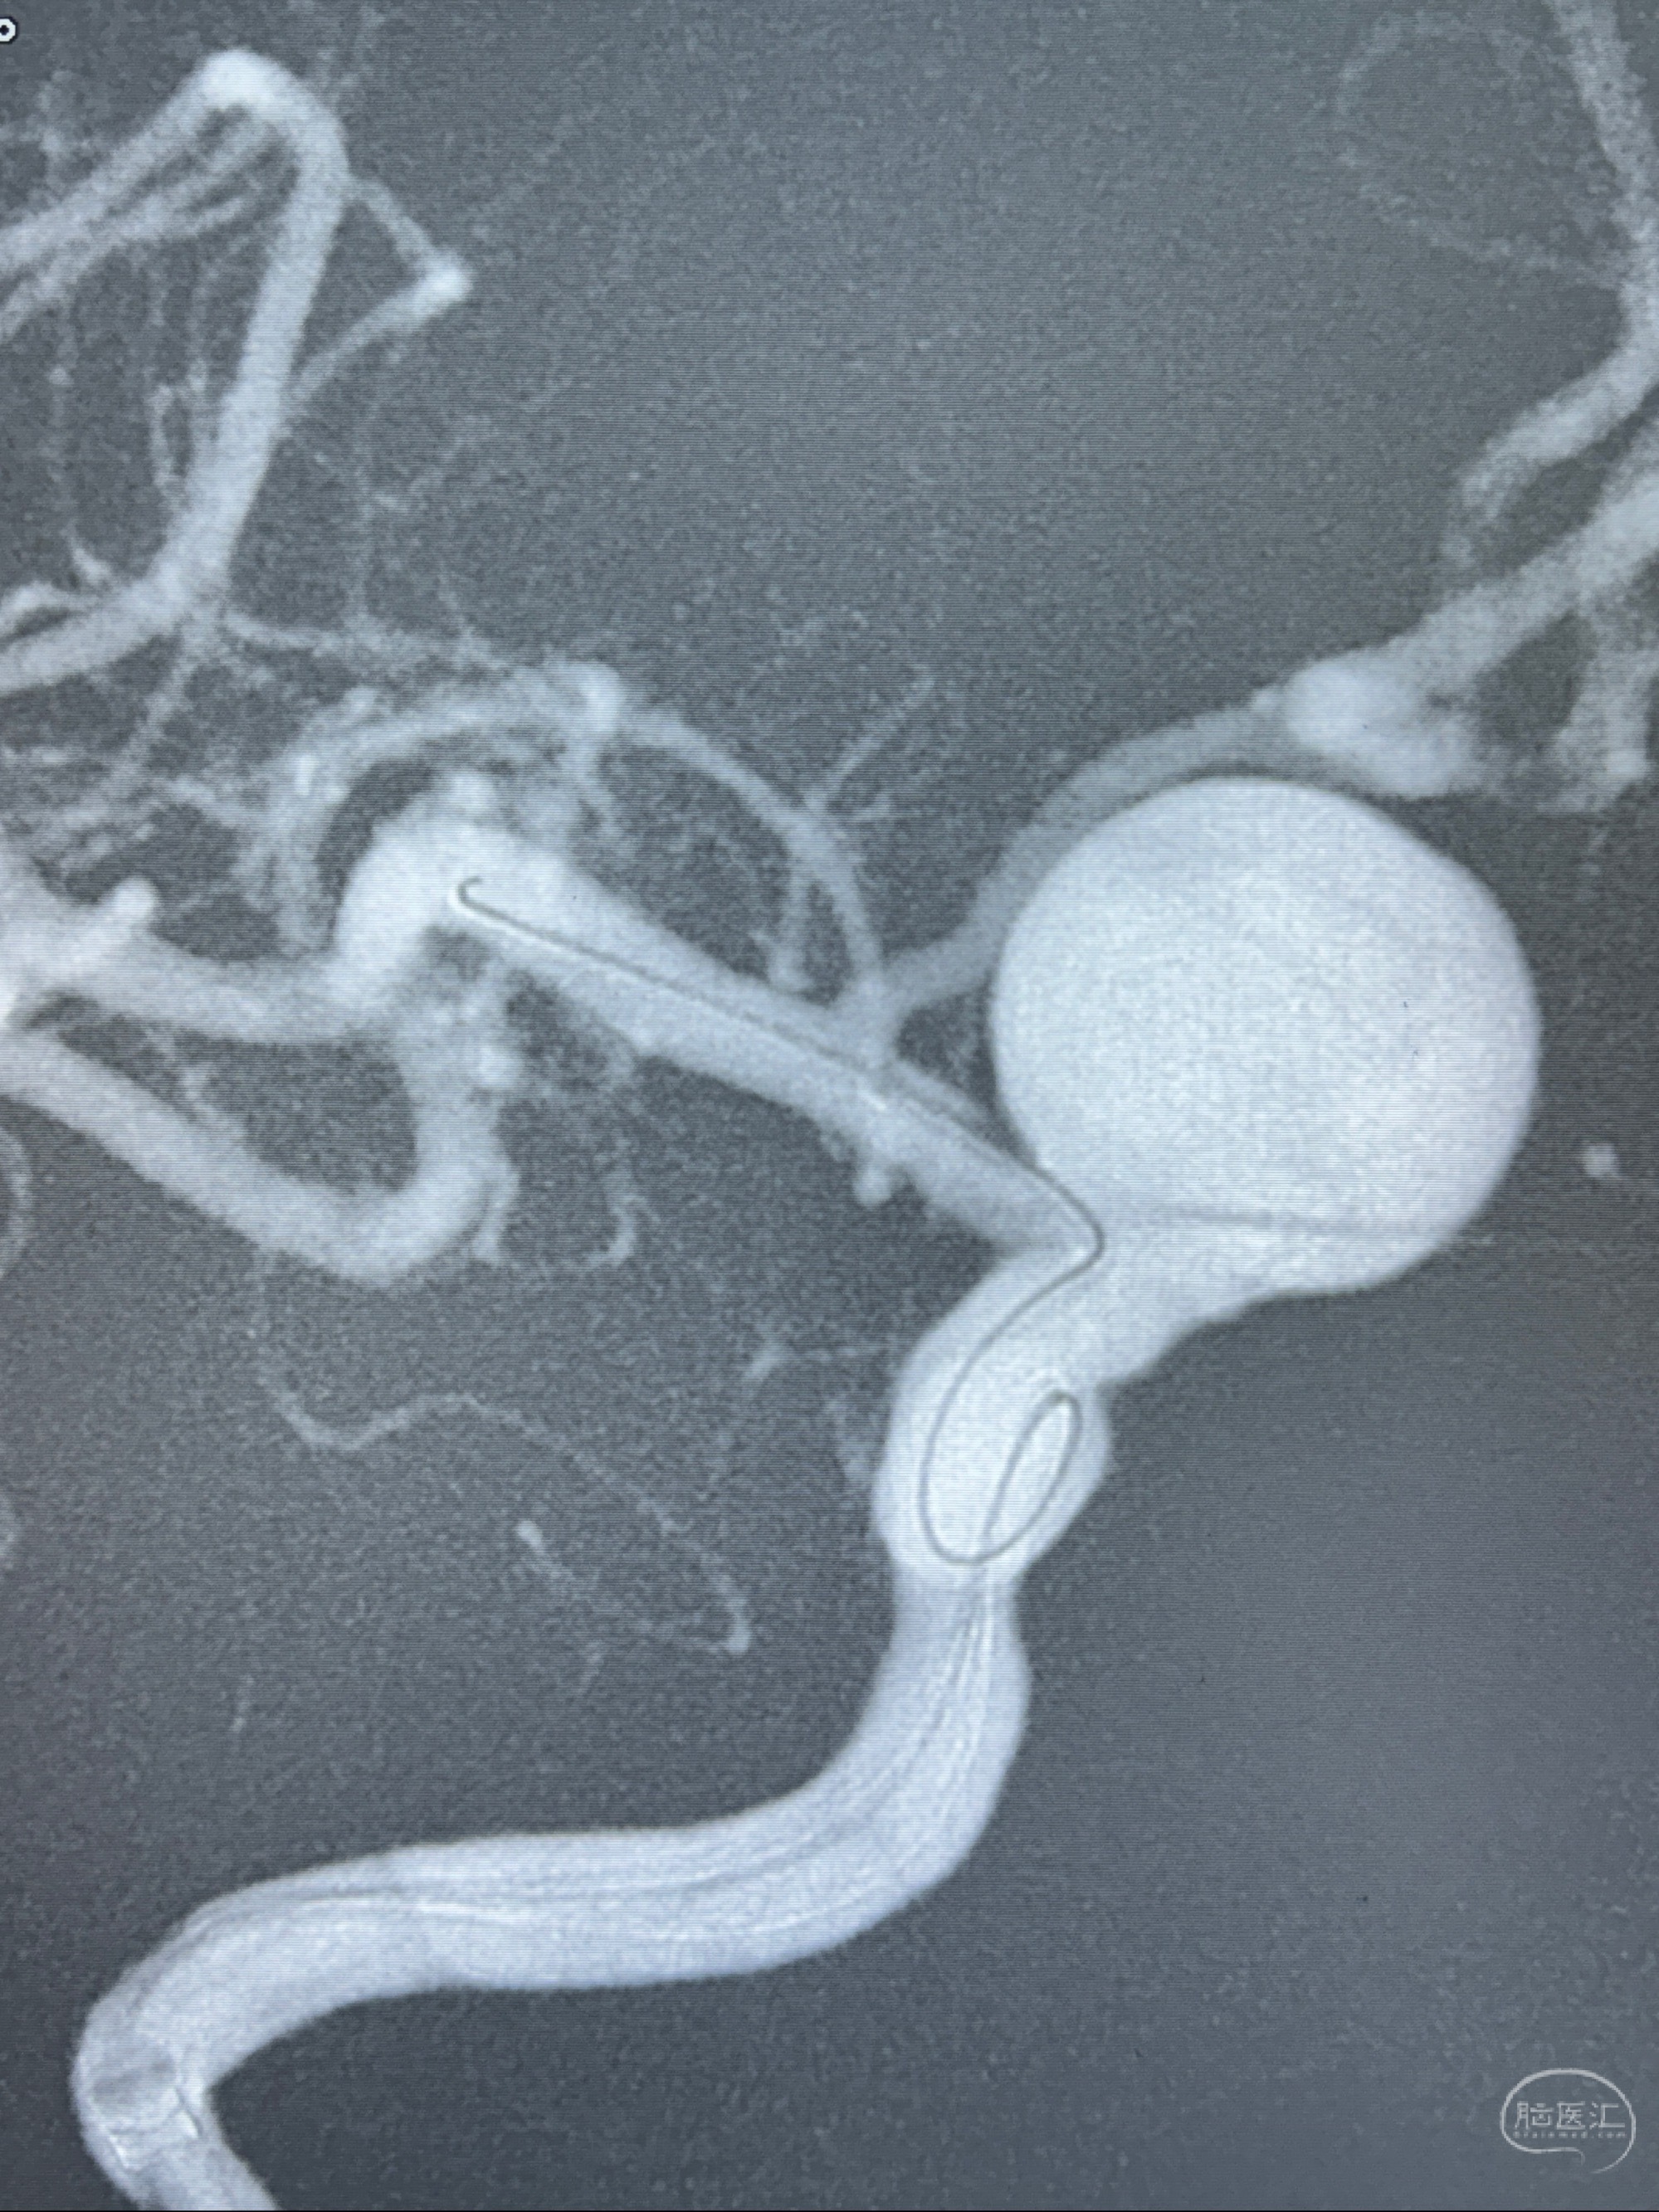

旋转3D展示动脉瘤局部的血管构筑

测量动脉瘤的大小:16*13.8*7.6mm大小,较原先变大,考虑双抗后瘤内血栓溶解可能

观察动脉瘤腔内的血流动力学情况